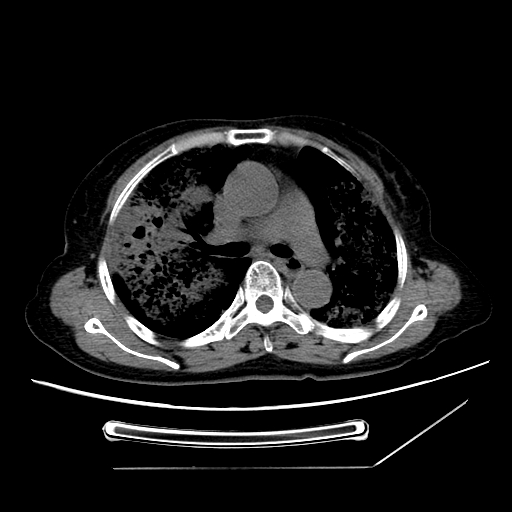

标题: CT25393:病人45岁,咳嗽,吐黄痰带血丝,发热,胸闷月余 [打印本页]

标题: CT25393:病人45岁,咳嗽,吐黄痰带血丝,发热,胸闷月余

1、左肺中央型肺癌并双肺弥漫性转移   2、双肺部感染    3、肺大泡     4、左侧胸腔积液

双侧肺弥漫性病变,可见“空泡征”及“蜂窝征”,考虑肺泡癌可能性大,左侧胸腔积液,考虑胸膜受累可能!

1)不排除肺泡癌可能。2)左侧胸腔积液。